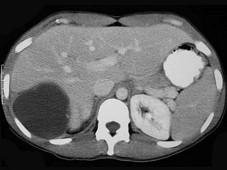

下列诊断肝包虫病的方法,错误的是 ( )A、B超B、补体结合试验C、诊断性穿刺D、间接血凝法试验E、包虫囊液皮内试验(Casoni试验)

问题 下列诊断肝包虫病的方法,错误的是 ( )

选项 A、B超 B、补体结合试验 C、诊断性穿刺 D、间接血凝法试验 E、包虫囊液皮内试验(Casoni试验)

答案 C